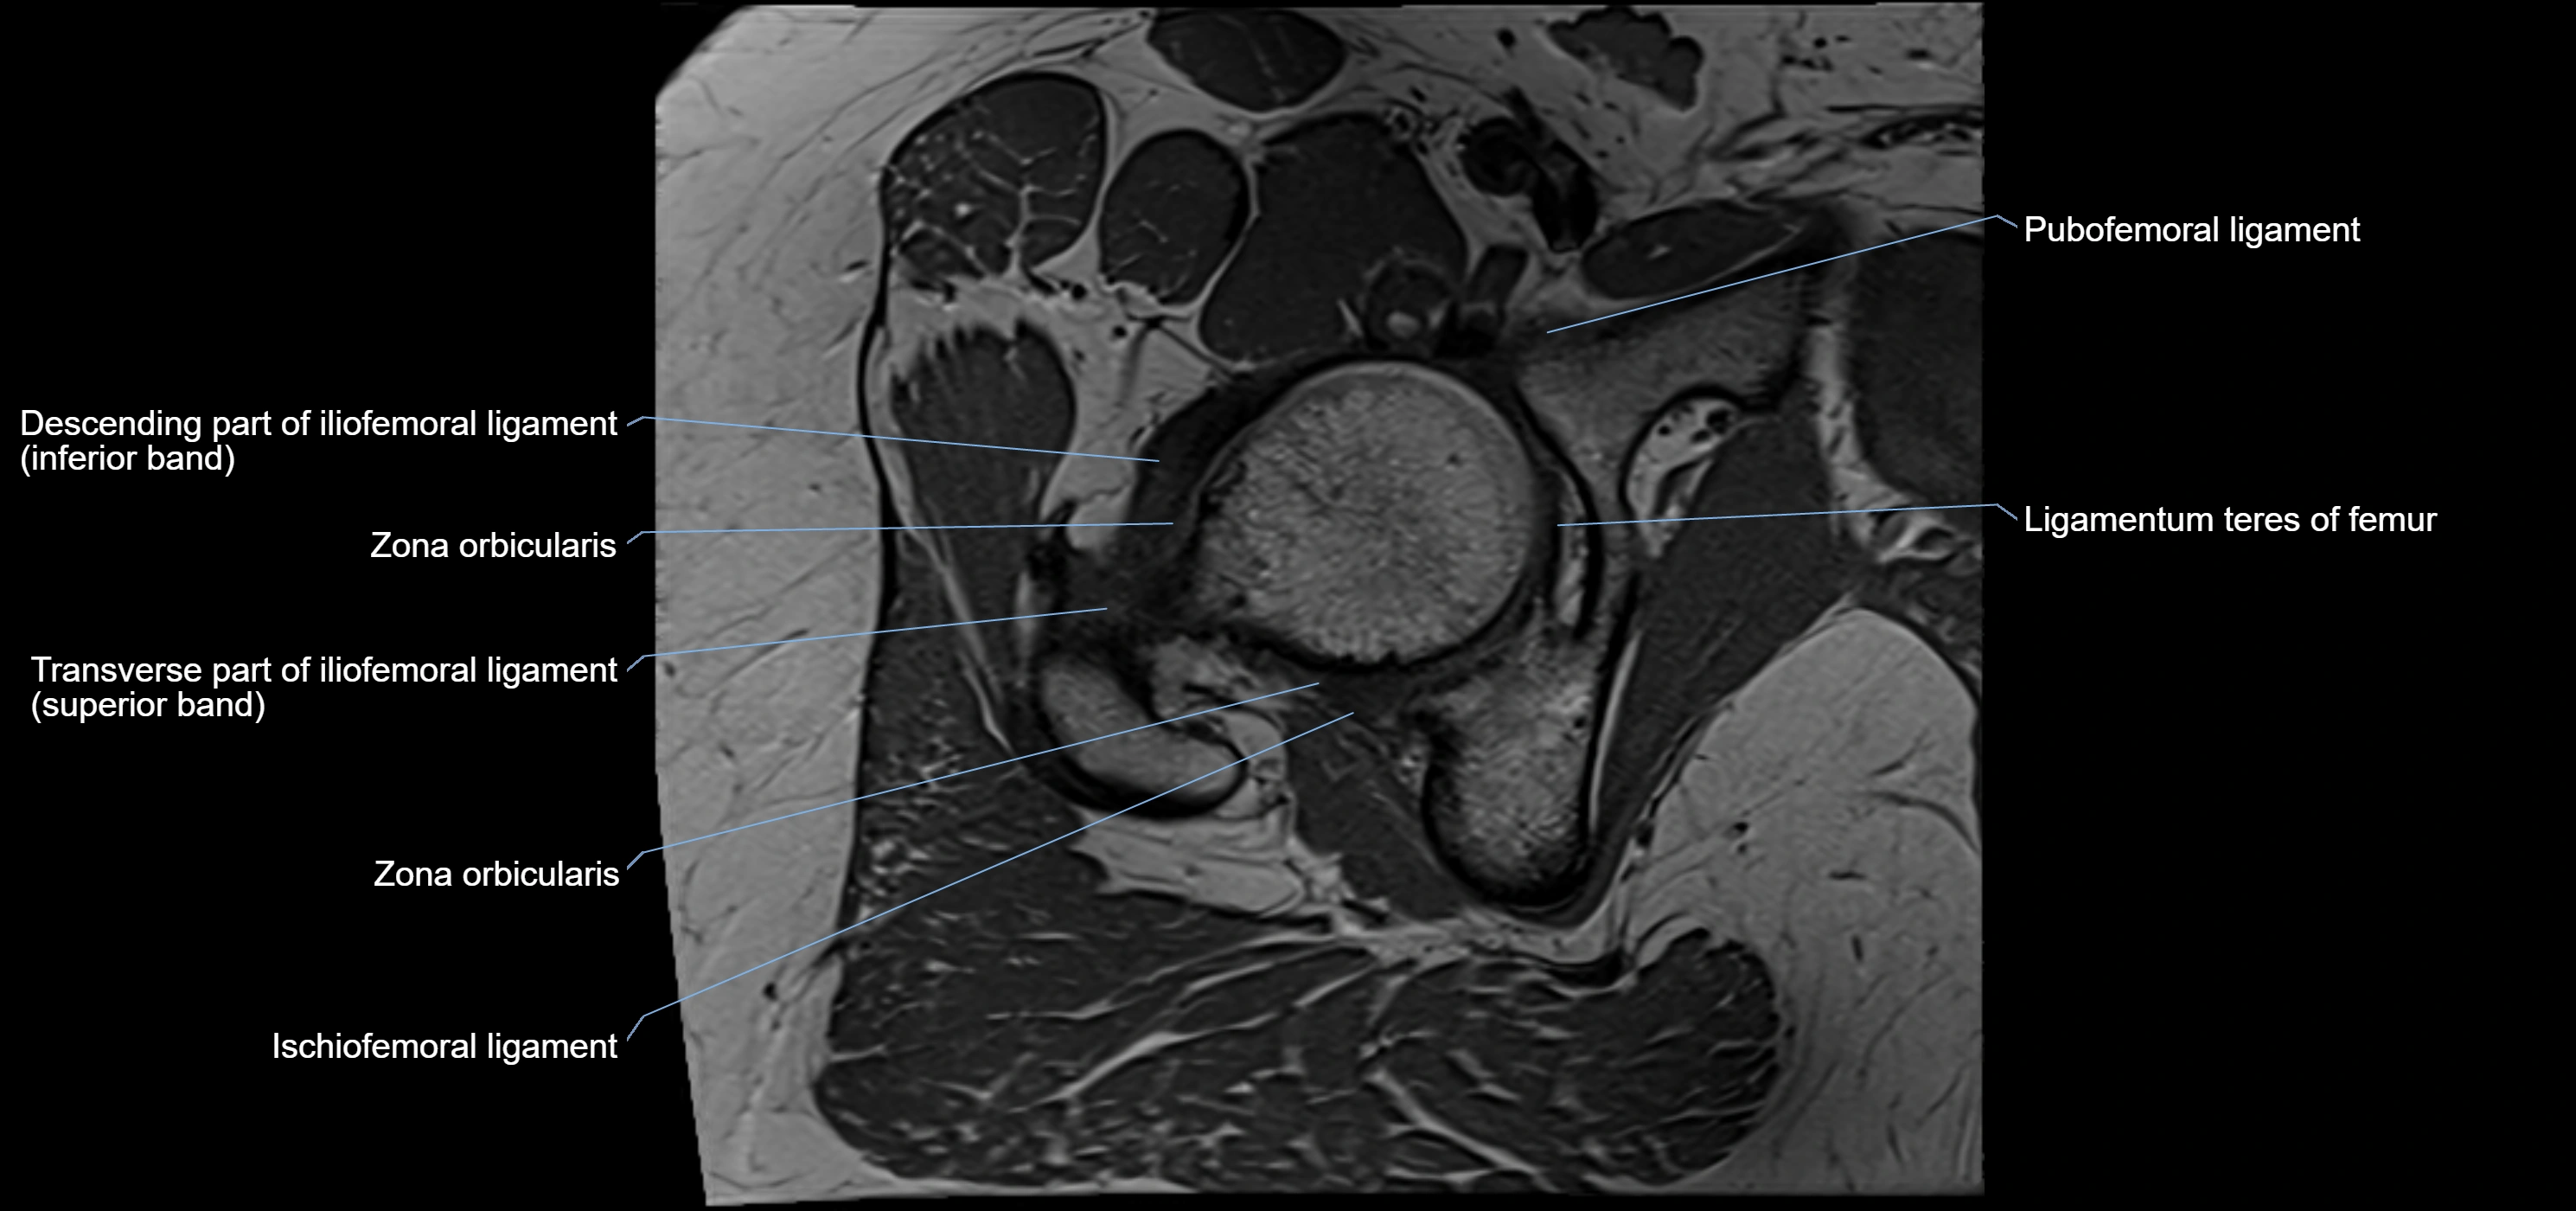

MRI image

image